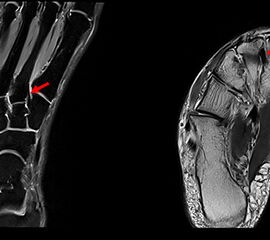

Das Lisfranc-Ligament selbst lässt sich am Besten im MRT beurteilen. Gelegentlich lässt sich im MRT ein Knochenmarksödem als einziges Zeichen einer nicht dislozierten Fraktur finden. Die MRT-Diagnostik ist allerdings eher unklaren interossären Erweiterungen bei persistierenden Schmerzen zur Suche nach isolierten Bandverletzungen vorbehalten 7511.

Zum Lesen der Bildbeschreibung und zur Vollansicht bitte das Bild anklicken.